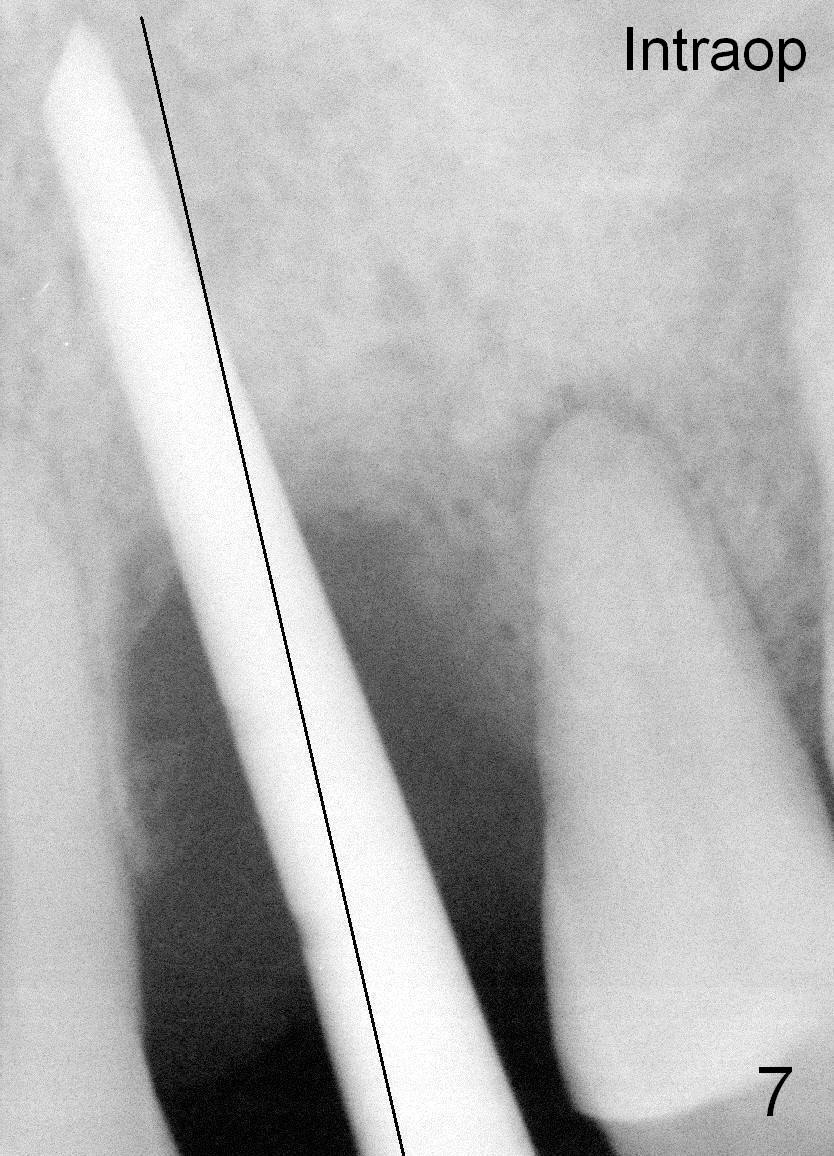

Fig.7: Black line: Change of osteotomy.